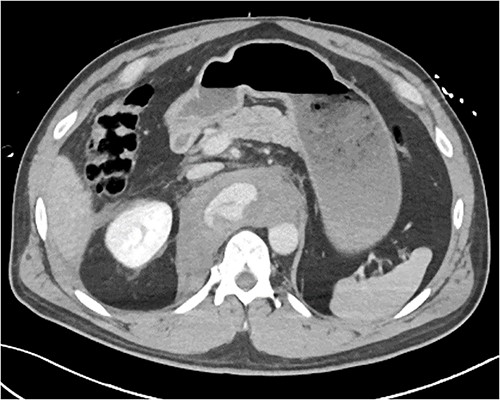

A 54-year-old male presented to our Level 1 Trauma Centre following a high-speed motor vehicle accident with rollover. Although initially haemodynamically stable, significant hypoxia prompted a trauma call activation. On arrival to the Trauma Centre, he had a Glasgow Coma Scale of 8 with an initial heart rate of 70 bpm and systolic blood pressure of 101 mmHg. A brief loss of cardiac output resulted in intubation, bilateral finger thoracostomies and the commencement of massive transfusion. Although his abdominal eFAST was positive, he was fluid responsive and proceeded to imaging. A full computed tomography (CT) trauma series demonstrated CA avulsion (Fig. 1) with contrast extravasation into the retroperitoneum and a large retroperitoneal haematoma measuring 18 cm by 9 cm (Figs 2 and 3). Nil visceral injury was identified and imaging otherwise revealed fractures of the left scapula, right 12th rib and bilateral acetabula and pubic rami.

Coronal CT slice demonstrating coeliac trunk avulsion with active bleeding into a large retroperitoneal haematoma.